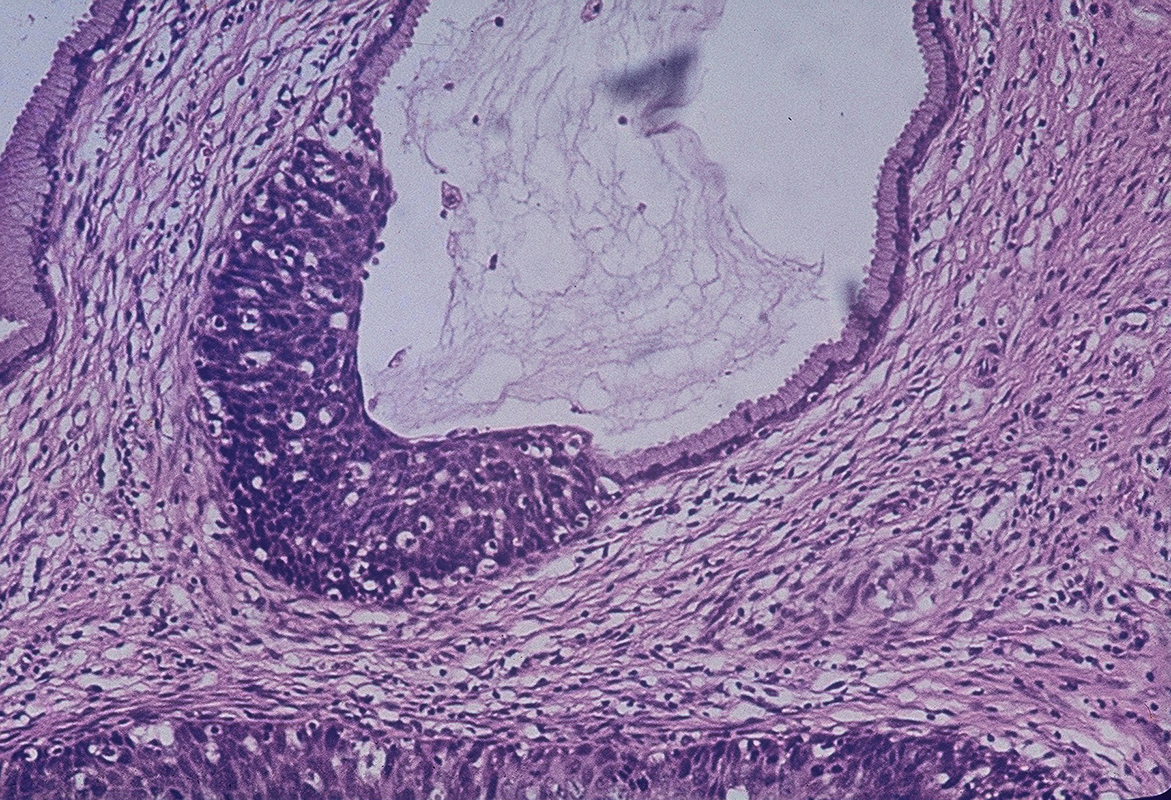

Before actual cancer cells in the cervix develop, the tissues of the at one time, cervical cancer was considered one of the most serious cancers for women.

Cervical cancer, or cancer of the cervix, begins on the surface of the cervix. Cervical cancer is a cancer arising from the cervix. This changes can be detected by regular cervical cancer. During cervical cancer awareness month, we asked dr. If cancerous cells have passed through a layer called the basement membrane. Early treatment often does not affect your ability to have children. Pap tests can detect precancerous conditions of the cervix, so they can be monitored or treated in order to prevent cervical cancer. Cervical cancer is a type of cancer that occurs in the cells of the cervix — the lower part of the uterus that connects to the vagina. Cervical cancer usually grows slowly, over many years. In the early stages of hpv infection, there are no symptoms, but as the cancer progresses the most common signs it is important to note that these symptoms are not specific for cervical cancer and can be caused by a variety of conditions. Learn more about the causes, symptoms, diagnosis, treatment, prevention, and outlook for cervical cancer. Deaths from cervical cancer could be eliminated if all women had regular pap smears. If cervical cancer is diagnosed, relieving symptoms remains an important part of cancer care and treatment.